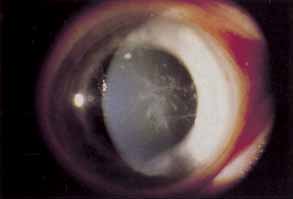

STERILE INFILTRATES

Sterile corneal infiltrates associated with contact lens wear are generally multiple, small, anterior stromal infiltrates found most often at the corneal limbus but also in clusters in the central cornea (Fig. 4).130–132 Rarely the epithelium alone may be involved and is commonly intact over stromal infiltrates. The anterior chamber may show mild to severe cellular reaction.130 Corneal infiltrates related to extended soft lens wear tend to form near the superior limbus.133 These infiltrates must be distinguished from their infectious counterparts, including chlamydia, by careful historical consideration and clinical examination.131 If there is any doubt regarding the etiology of the infiltrates, scrapings for stain and culture should be taken, followed by appropriate broad-spectrum topical antibiotic therapy.

Fig. 4 Twelve o'clock sterile marginal corneal infiltrate.

Using rigid gas permeable lens wear as the referent, soft lens wearers and particularly extended soft lens wearers carry a significantly higher risk of developing sterile infiltrates.6,9,130,134 PMMA lens wearers are the least likely to suffer this complication.134 A longer duration of soft lens wear provides a proportionately increased risk of developing these infiltrates.132,135 The rate of sterile infiltrates per year for disposable extended soft lens wear in a prospective study was as high as 7%, suggesting that disposable lenses are not the solution to this problem.136 Daily disposable soft lenses or soft silicone hydrogel lenses afford the lowest rate of peripheral infiltrates for soft lens wear.22,132

Various theoretic causes include chemical hypersensitivities to thimerosal and chlorhexidine, exposure to a variety of environmental toxins through digital contamination, improper enzyme use, staphylococcal lid disease, and bacterial contaminants of contact lens cases.130,137 Antigenic debris held chronically against the corneal surface has been cited as a potential basis for sterile infiltrates, particularly with extended soft lens wear.130–134

Required therapy consists of discontinuing lens wear and treating cautiously with topical corticosteroids, a practice that necessitates frequent initial examinations.130 Lens wear should cease until there is complete resolution of all infiltrates and adequate corticosteroid taper. Recurrences may be avoided by careful review of contact lens care and handling, cessation of suspected offending chemicals, insistence on clean contact lens cases and treatment of any associated staphylococcal lid disease. Recurrent infiltrates associated with extended soft lens wear may require the use of soft or rigid daily wear lenses. Daily disposable and silicone hydrogel soft lenses are an excellent strategy for prevention in susceptible individuals. The prognosis for the majority is good, with visual loss remaining rare.